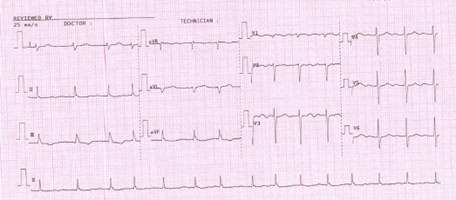

Relevant Test Results Prior to Catheterization

Initial ECG revealed AF. Transthoracic echocardiography revealed concentric LVH with a 70 % of left ventricular systolic function, normal right ventricular systolic function, bi-atrial enlargement and severe calcific aortic stenosis which classified as stage D1 (AVA 0.98 cm2 by AV VTI, AV Vmax 4.03 m/s, mean AV pressure gradient 38.21 mmHg). Following as the Heart Team discussion, Transcatheter Aortic Replacement (TAVR) following coronary angiography (CAG) was scheduled as the optimal choice.